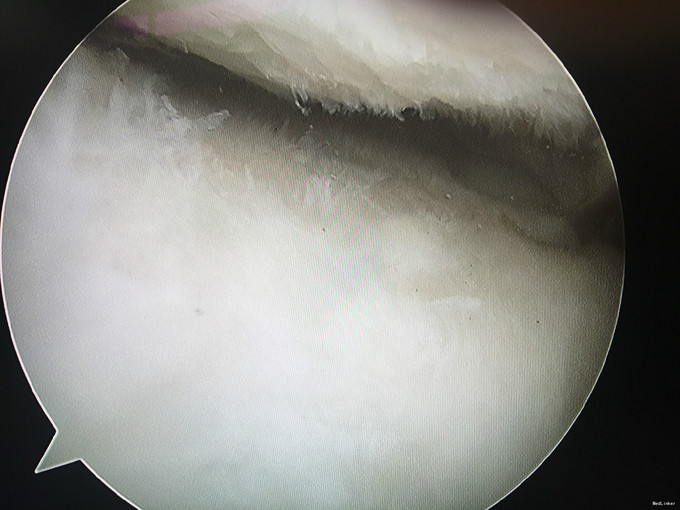

入院诊断:左膝半月板损伤、左膝前交叉韧带损伤 治疗:入院后行左膝关节镜下外侧半月板成形+髁间窝成形+前交叉韧带自体肌腱重建手术。

随访:患者因为病程较长(十余年),术后3月膝关节才恢复正常活动度,行走正常。建议其术后1年再恢复正常运动。 讨论:该病例膝关节损伤时间较长,手术时关节已表现为提早退变(患者年龄并不大)。在前交叉韧带重建前,需要对其狭窄的髁间窝进行成形。术后恢复时间也较一般情况下延长。因此,建议关节出现病损应及时诊治。